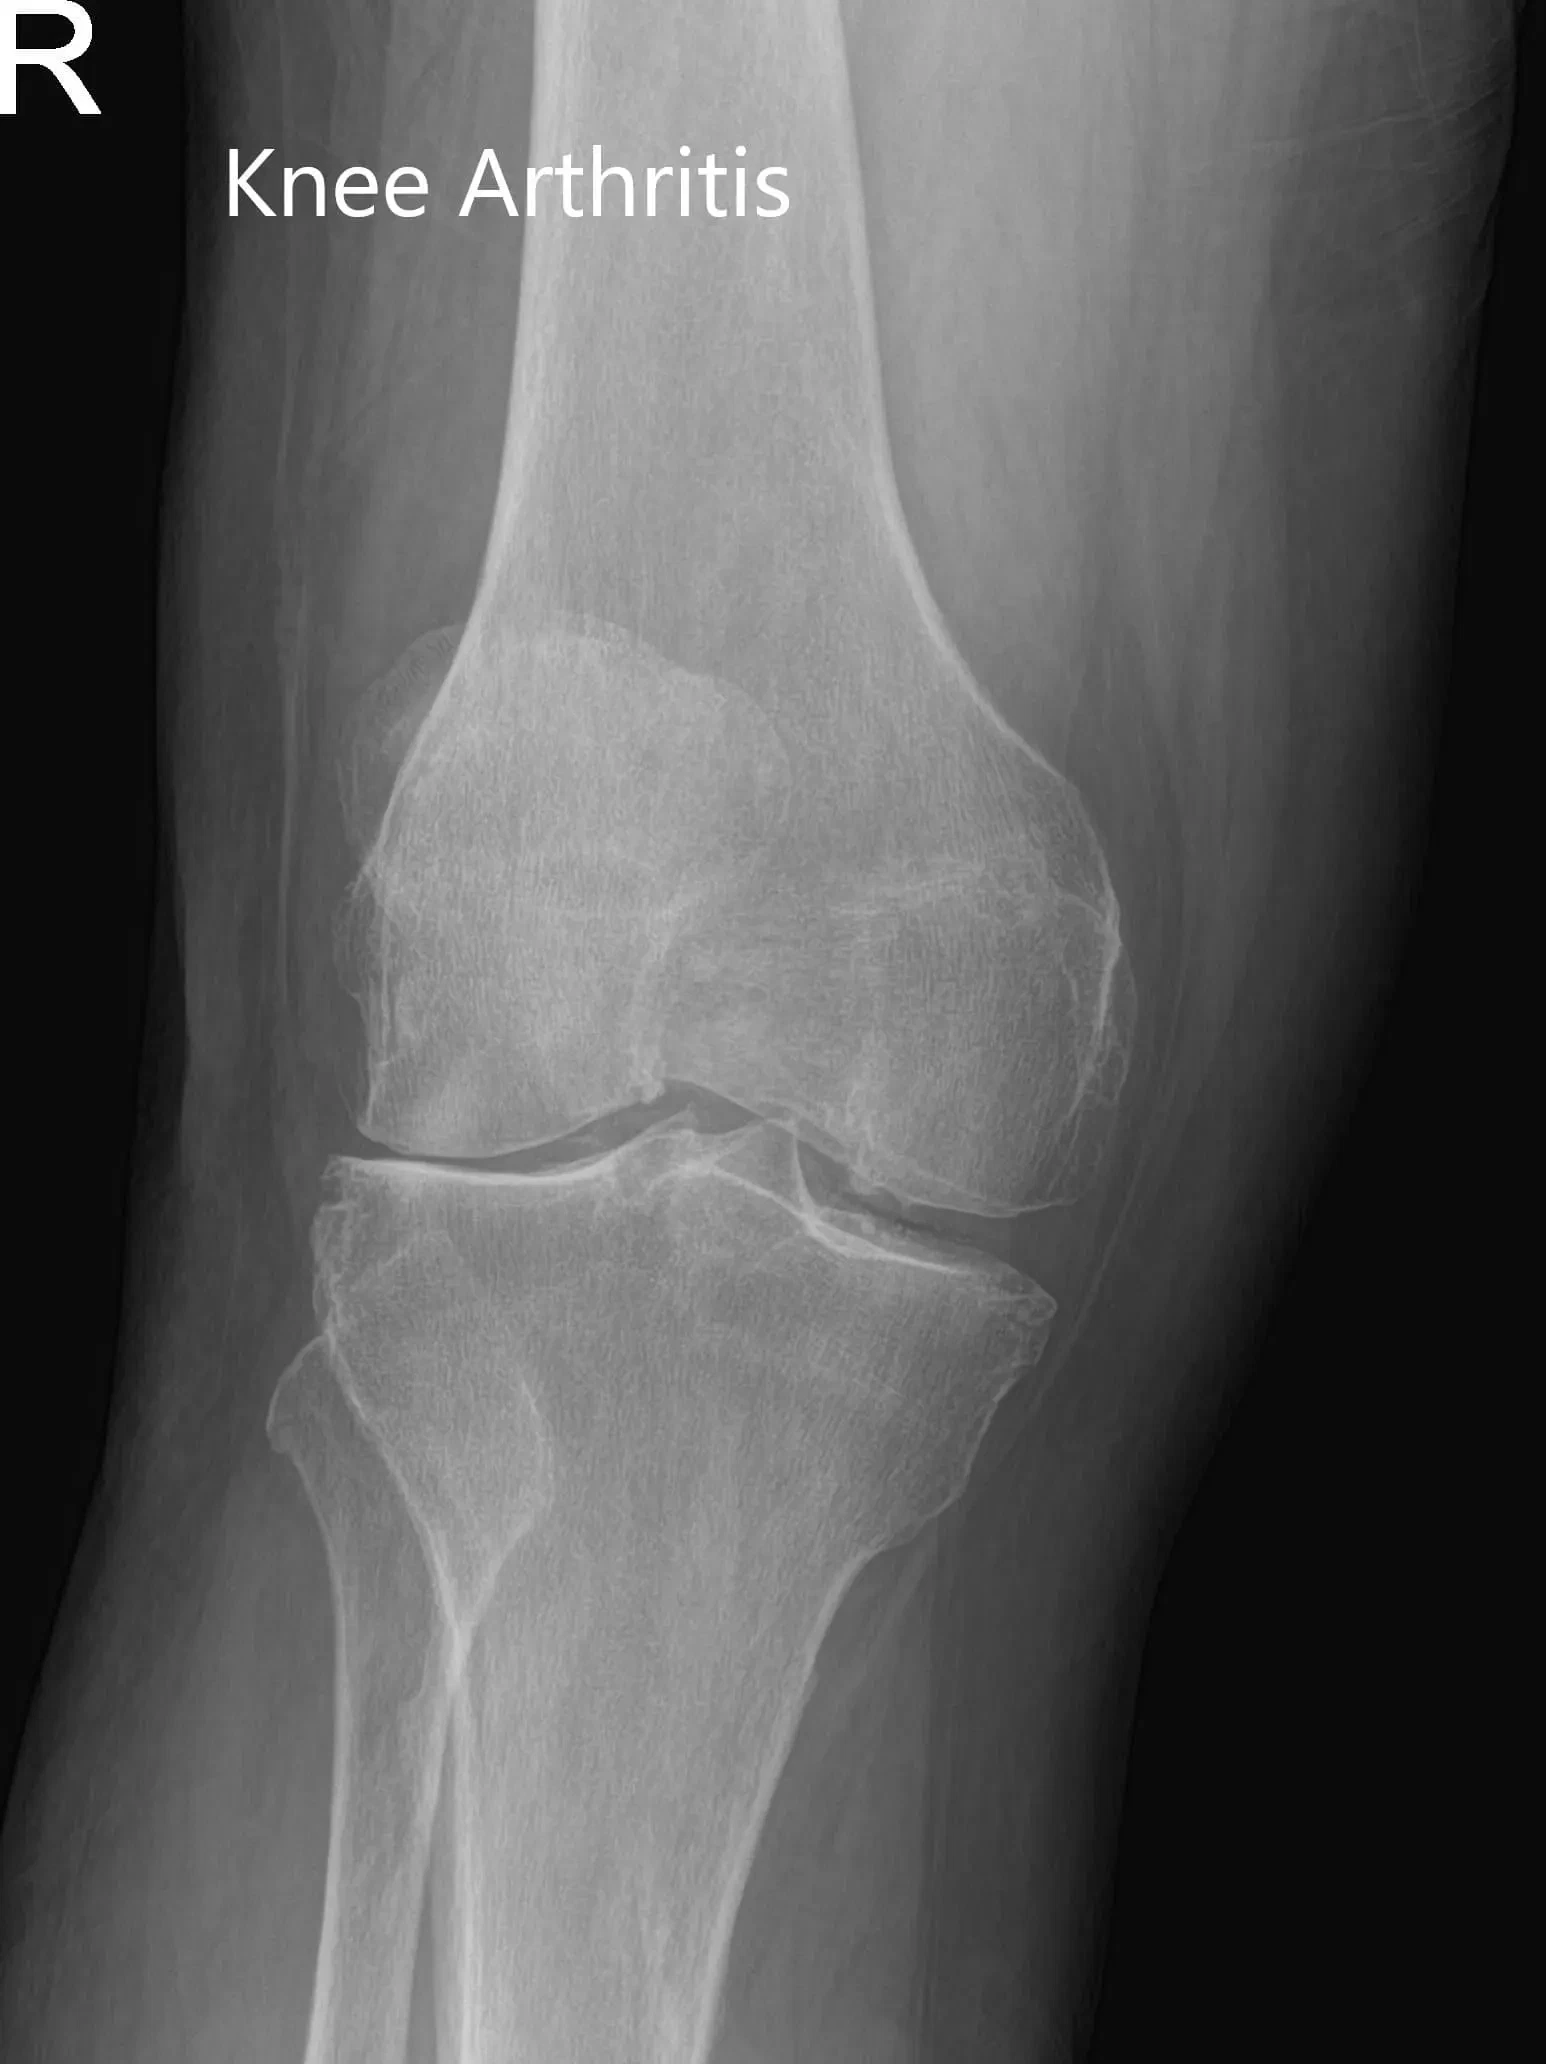

Imaging studies revealed severe bilateral knee arthritis. The right knee was worse than the left side. She was advised right total knee replacement with custom instruments. Risks, benefits, and alternatives were discussed at length with her. She agreed with the plan.

X-ray of the right knee in anteroposterior and lateral views.